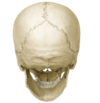

1

Q

A

Norma verticalis/superior aspect